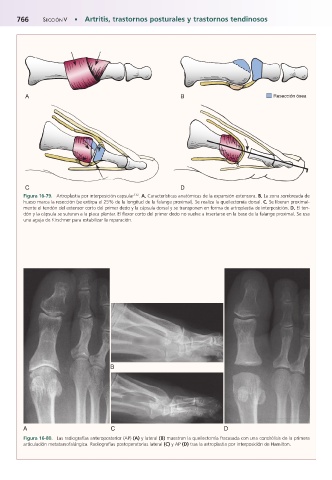

Figura 16-79.mArtroplastia por interposición capsular 132 . A, Características anatómicas de la expansión extensora. B, La zona sombreada de

hueso marca la resección (se extirpa el 25% de la longitud de la falange proximal). Se realiza la queilectomía dorsal. C, Se liberan proximal-

mente el tendón del extensor corto del primer dedo y la cápsula dorsal y se transponen en forma de artroplastia de interposición. D, El ten-

dón y la cápsula se suturan a la placa plantar. El flexor corto del primer dedo no vuelve a insertarse en la base de la falange proximal. Se usa

una aguja de Kirschner para estabilizar la reparación.

Figura 16-80.mLas radiografías anteroposterior (AP) (A) y lateral (B) muestran la queilectomía fracasada con una condrólisis de la primera

articulación metatarsofalángica. Radiografías postoperatorias lateral (C) y AP (D) tras la artroplastia por interposición de Hamilton.